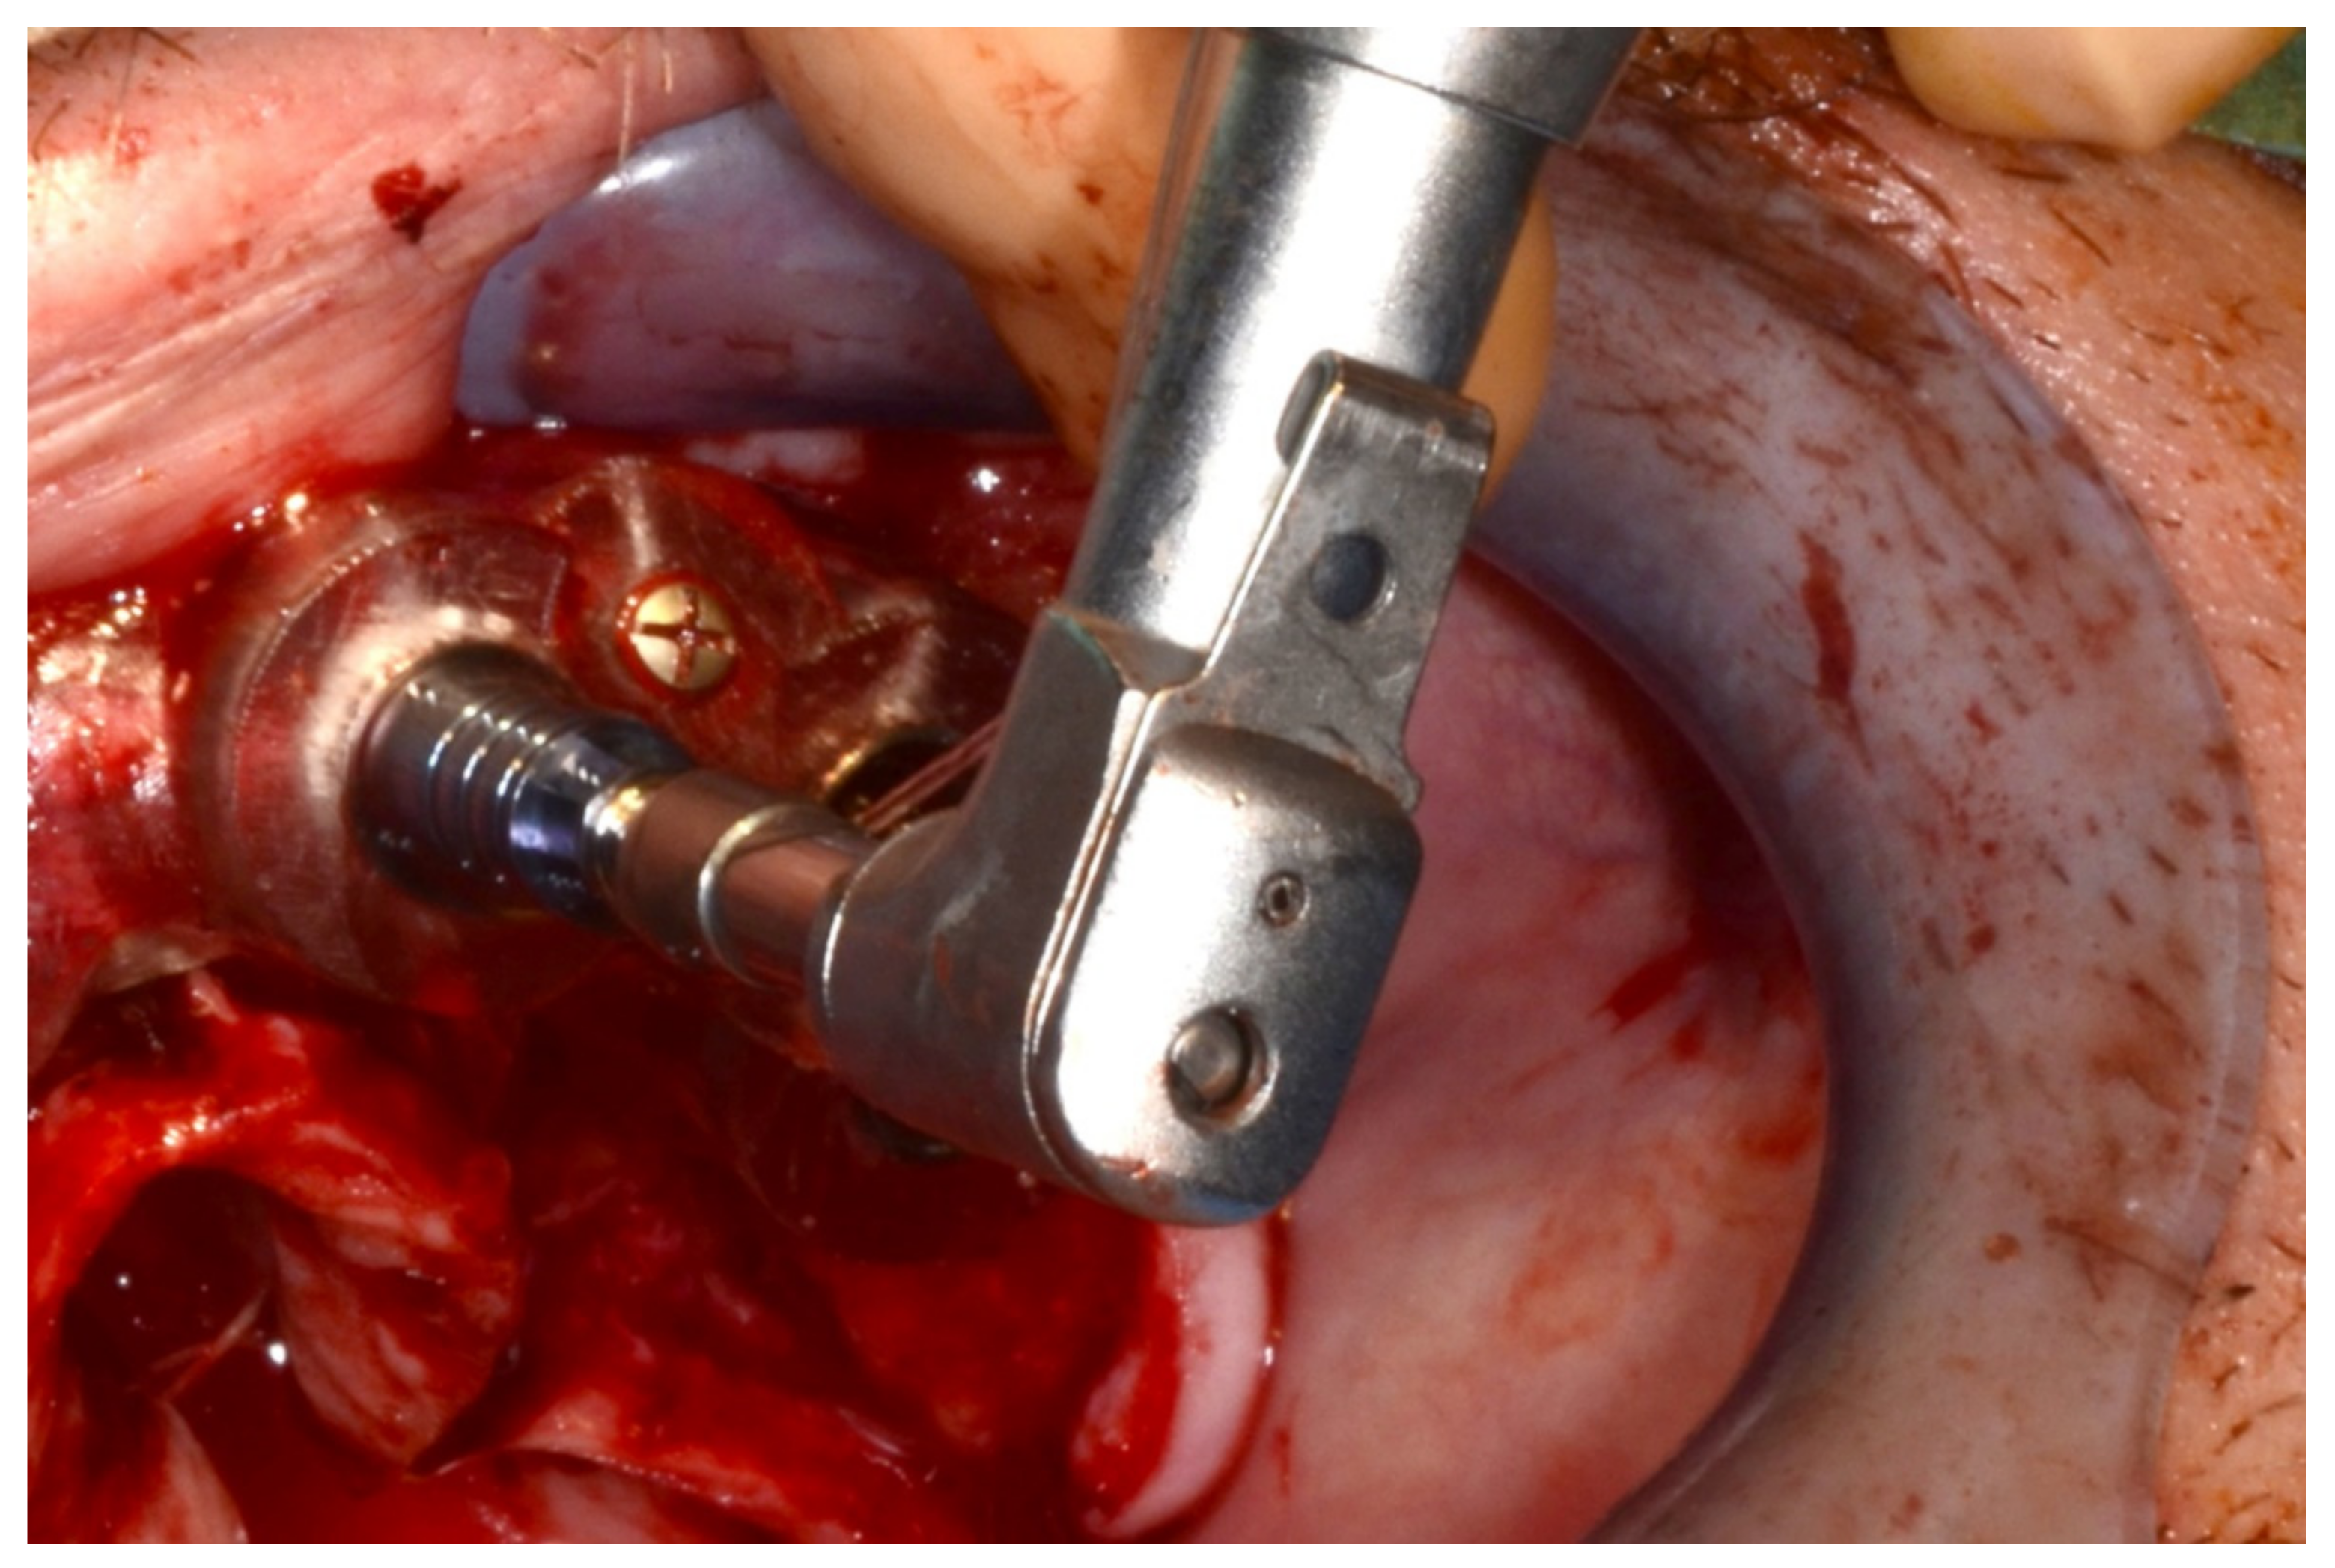

In November 2017, two guided dental implants were placed at sites # 12 and # 21 (Figure 7, Figure 8, Figure 9, Figure 10 and Figure 11).

Implant bed preparation by using guided drills inserted into specific ad hoc drill handles.

Figure 9.

Figure 11.

Lateral verification of the parallel placement of the implants.